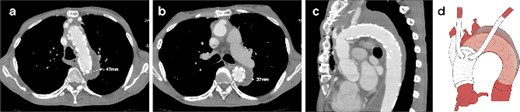

A 62-year-old male presented at the previous hospital with left hemiplegia. Computed tomography (CT) detected an aortic dissection with malperfusion of the right brachiocephalic artery, necessitating a referral to our institution. Preoperative CT showed the primary entry tear in the distal aortic arch and a patent false lumen. A total arch replacement was successfully performed using the fenestrated FET technique. The surgical procedure involved median sternotomy, establishment of extracorporeal circulation with right atrial drainage and perfusion via right axillary artery, circulatory arrest at 28°C and selective cerebral perfusion to perfuse all cervical vessels. Myocardial protection was provided by retrograde cardioplegia. Following resection of the aorta at zone 1, FET was inserted and deployed into the aorta, perfusing blood from the femoral artery. Fenestration of the graft at the ostium of the second and third cervical branches was performed. A U-shaped graft was placed around cervical branches, and three 4-0 polypropylene U-shaped sutures were roughly placed to fix the open stent graft, leaving some gaps between the sutures. Subsequent procedures included anastomosis of a four-branch graft to the distal aorta, reconstruction of the brachiocephalic artery and proximal anastomosis. Postoperative contrast-enhanced CT on day 5 showed no endoleak and favorable remodeling of the descending aorta (Fig. 1). However, after 6 months, follow-up CT detected a fenestration-related endoleak and an enlarged aortic arch (Fig. 2), prompting reoperation. The reoperation involved median re-sternotomy, establishment of extracorporeal circulation with right femoral vein drainage and perfusion via an 8-mm graft anastomosed to the left axillary artery, circulatory arrest at 28°C, and selective cerebral perfusion to perfuse all cervical vessels. Upon opening the artificial graft, it was observed that the stent graft had some gap between fixed U-sutures and had become detached from the aorta, revealing a small entry adjacent to it, which communicated with the false lumen. The left subclavian artery (LSCA) was ligated, and the left common carotid artery was transected at its origin and sutured. An open stent was inserted distally, followed by placement of a felt strip and a 4-0 running suture. Subsequent procedures included anastomosis of a four-branch graft to the distal aorta, reconstruction of the three cervical branches and proximal anastomosis. The surgery was completed without complications. Postoperative contrast-enhanced CT on day 5 revealed resolution of the endoleak with no blood flow into the false lumen of the arch. Follow-up CT 3 months after discharge revealed favorable remodeling of the aortic arch (Fig. 3).

CT 6 months after the initial surgery reveals an endoleak from the fenestration (indicated by the white arrow), antegrade flow in the false lumen, and an enlarged aorta at the levels of the aortic arch (a) and the carina of the trachea (b). Sagittal image (c). An illustrative diagram (d) shows the schema of endoleak from fenestration (indicated by the black arrow).